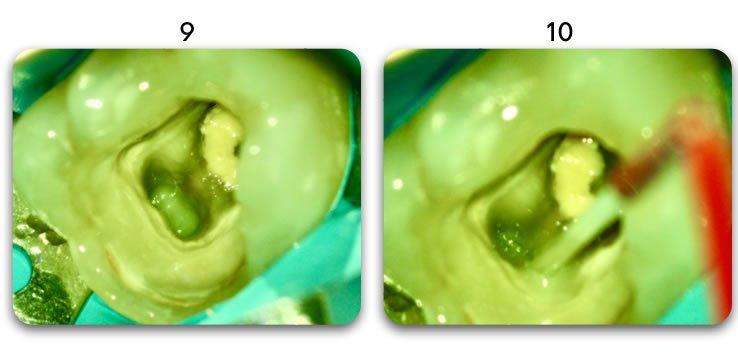

Template for x-rays